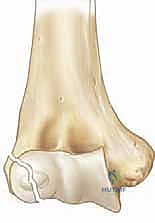

يُعرف كسر اللقيمة الوحشية للعضد بأنه انفصال أو تهشم يصيب الجزء الخارجي (الوحشي) من النهاية السفلية لعظم العضد (العظم العلوي للذراع) بالقرب من مفصل الكوع. هذه الكسور ليست نادرة على الإطلاق؛ فهي تمثل ما بين 10% إلى 20% من إجمالي كسور الكوع عند الأطفال، وتأتي في المرتبة الثانية مباشرة بعد كسور فوق اللقمتين (Supracondylar fractures). تكمن خطورة هذا الكسر في أنه يمتد عادة ليخترق سطح المفصل نفسه، والأخطر من ذلك أنه يمر عبر "صفيحة النمو" (Growth Plate) وهي المنطقة الغضروفية الحساسة المسؤولة عن نمو العظم وتطوره الطبيعي.

لماذا الكسر مخادع؟ في الأطفال الصغار، تكون أجزاء كبيرة من مفصل الكوع عبارة عن غضاريف لم تتحول إلى عظم صلب بعد (لم تتعظم). الأشعة السينية لا تظهر الغضاريف، بل تظهر العظام فقط. لذلك، قد يبدو الكسر في الأشعة صغيراً جداً (مجرد قشرة عظمية صغيرة مكسورة)، بينما في الواقع، هناك كتلة غضروفية كبيرة جداً (تحتوي على سطح المفصل وصفيحة النمو) قد انفصلت تماماً وتدور حول نفسها.

هنا تتجلى خبرة الجراح. الطبيب غير المتخصص قد يرى الأشعة ويقول للآباء "إنه كسر بسيط يحتاج لجبس"، بينما الخبير مثل أ.د. محمد هطيف يدرك من خلال النظرية التشريحية وخبرته الطويلة أن هذا الكسر غير مستقر ويحتاج لتدخل جراحي.

* الدرجة الأولى (Stage 1): الكسر غير متحرك من مكانه (أقل من 2 ملم)، والمفصل سليم.